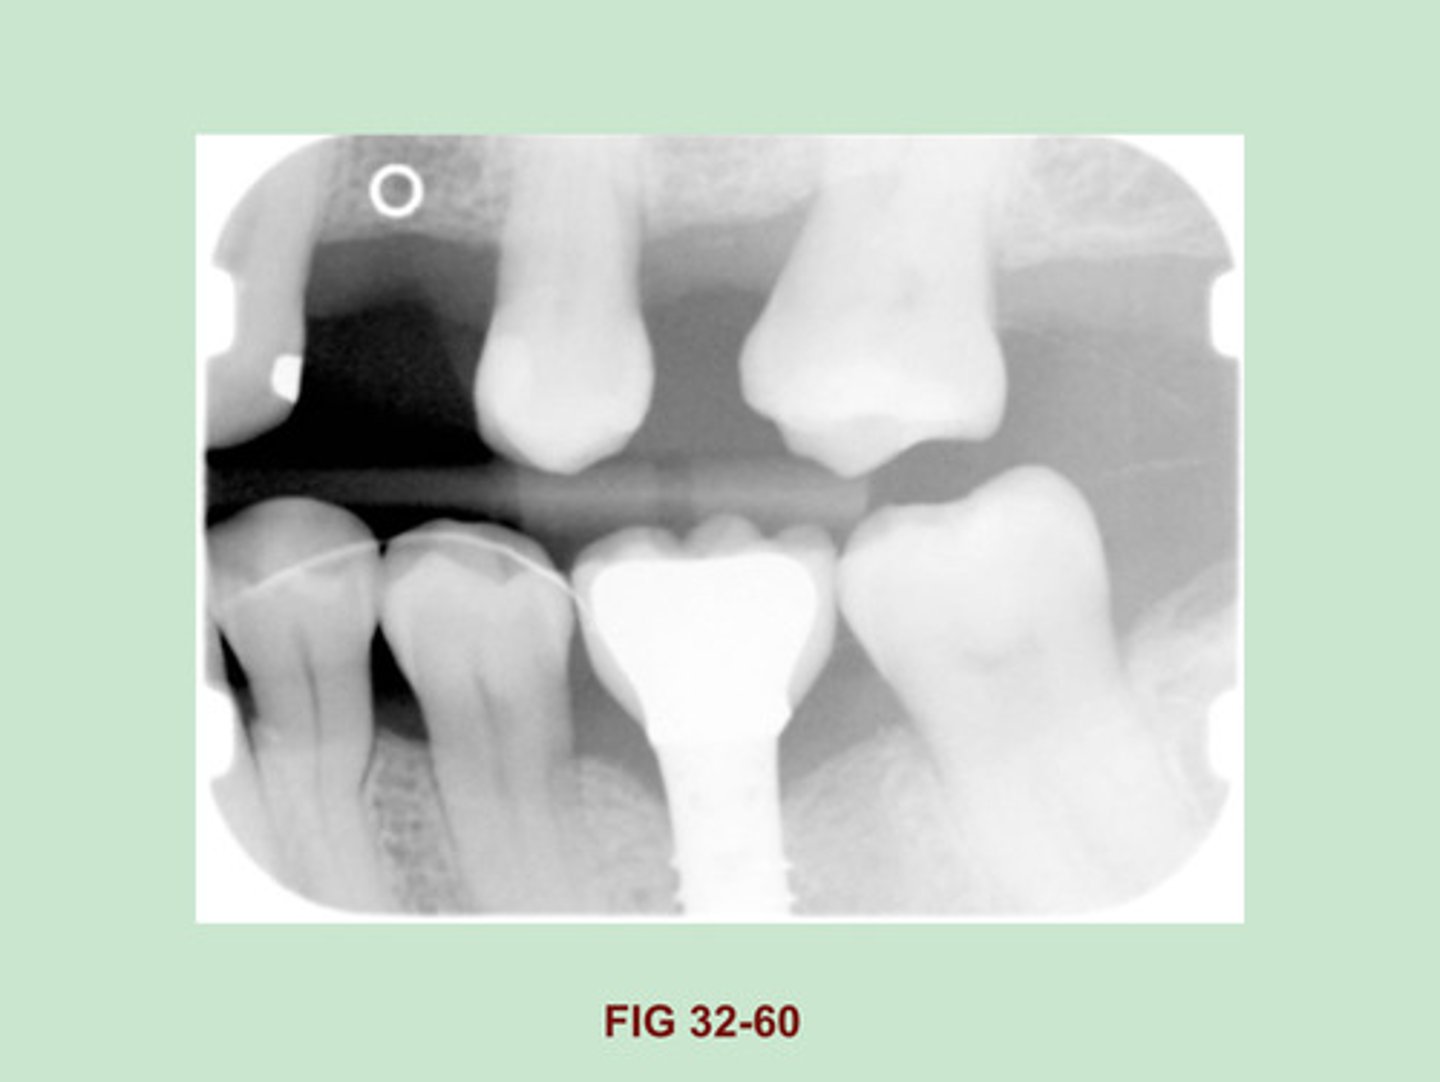

Identify the RESTORATION PRESENT in the area of the MANDIBULAR FIRST MOLAR. (Figure 32-60).

Dental Implant (porcelain fused to metal)

Side Note: Implants are being used in oral surgery w/ INCREASED frequency. The appearance of the numerous ENDOSTEAL implants that are currently used vary. depending on their shapes & design. the ENDOSTEAL implant is made of a metallic material & appears radiopaque on a dental image.